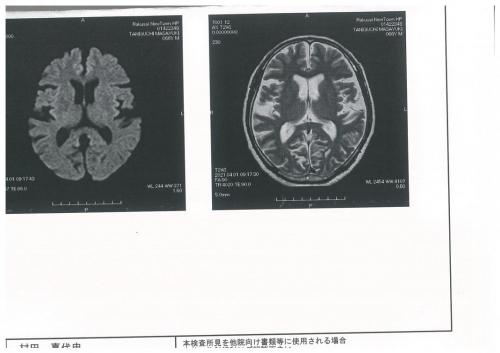

↓ ↓ ↓ 谷口さんの脳の画像です。

本人の許可をもらいました↓ ↓ ↓

結果は・・・問題なし!

脳委縮度や脳動脈の狭窄や瘤も問題なし!